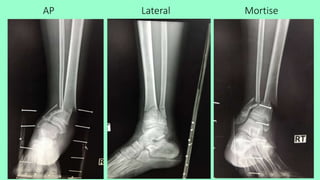

• Film right ankle AP, lateral, Mortise

AP Lateral Mortise

• Close transverse fracture right distal tibia with minimal displacement

• Close multifragmentary fracture right distal fibula with displacement